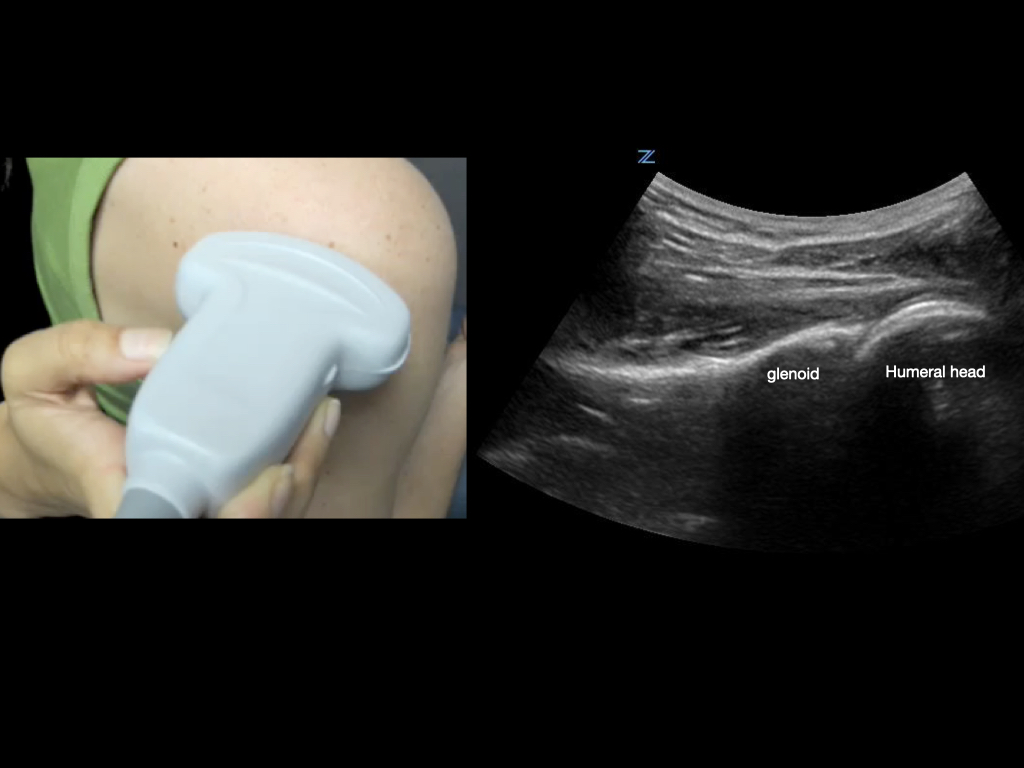

To best view the shoulder joint, consider using a curvilinear transducer. Align the transducer parallel and just inferior to the scapular spine, and slide the transducer out laterally until you are centered on the humeral head and glenoid.

Figure 4.

Transducer orientation when scanning the glenohumeral joint.